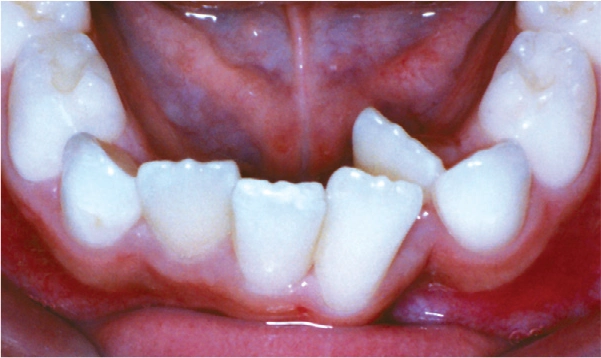

Crowding

Malocclusions, like those illustrated above, may benefit from early diagnosis through full orthodontic examination.